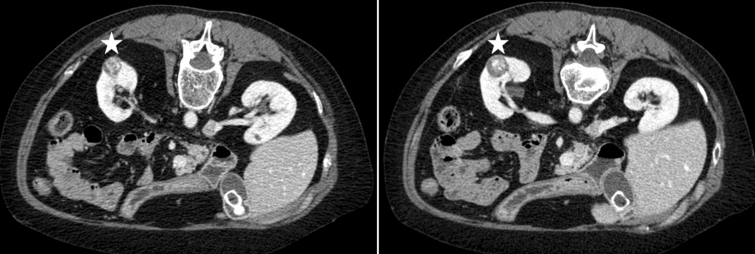

One patient experienced intraoperative and postoperative bleeding, resulting in a total blood loss of 1300 ml (#1 in Table 4). This patient needed therapeutic anticoagulation and immunosuppression due to history of chronic thromboembolic pulmonary hypertension and subsequent lung transplantation. The renal artery could not be separated adequately because of adhesions of the renal hilum. The tumor appeared hypervascular. The surgery was performed laparoscopically with zero ischemia and Hemopatch® exclusively as HA. An additional port for suction was necessary to handle intraoperative bleeding. On postoperative day 1, a laparotomy (via Chevron incision) was performed because of postoperative bleeding. Length of wound drainage and hospital stay were 11 and 19 days, respectively. The complication was classified as Clavien–Dindo 3. In total, 10 erythrocyte concentrates and six fresh frozen plasma transfusions were applied. This single tumor was preoperatively assessed as 20 mm in width, PADUA score 8, and RENAL nephrometry score 8. Preoperative scans of this case are shown in Fig. 1. Histopathologic evaluation revealed a clear cell RCC, pT1a G2 pR0.

Fig. 1.

Exemplary preoperative CT scans of one case (patient #1 in Table 4) with intra- and postoperative bleeding (transverse plane; renal lesion in left kidney marked with a star)